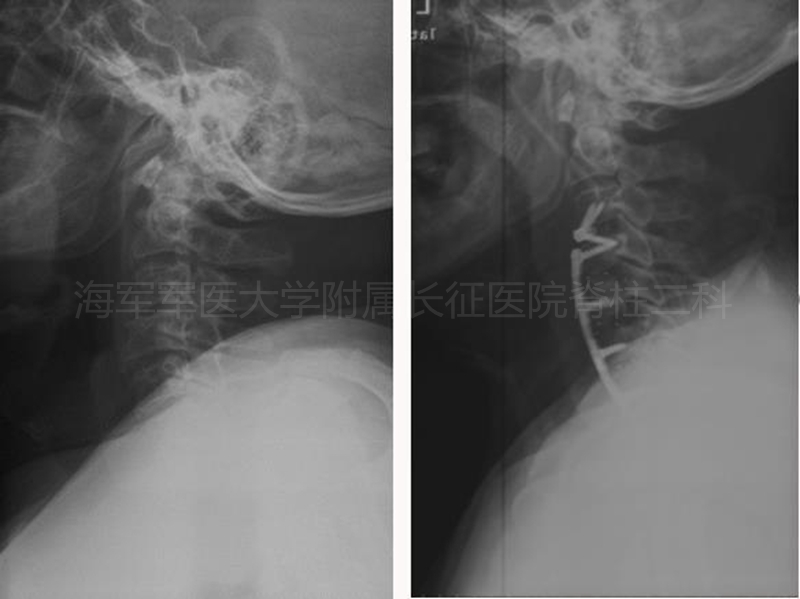

术前、术后侧位平片对比

术前、术后矢状位CT对比